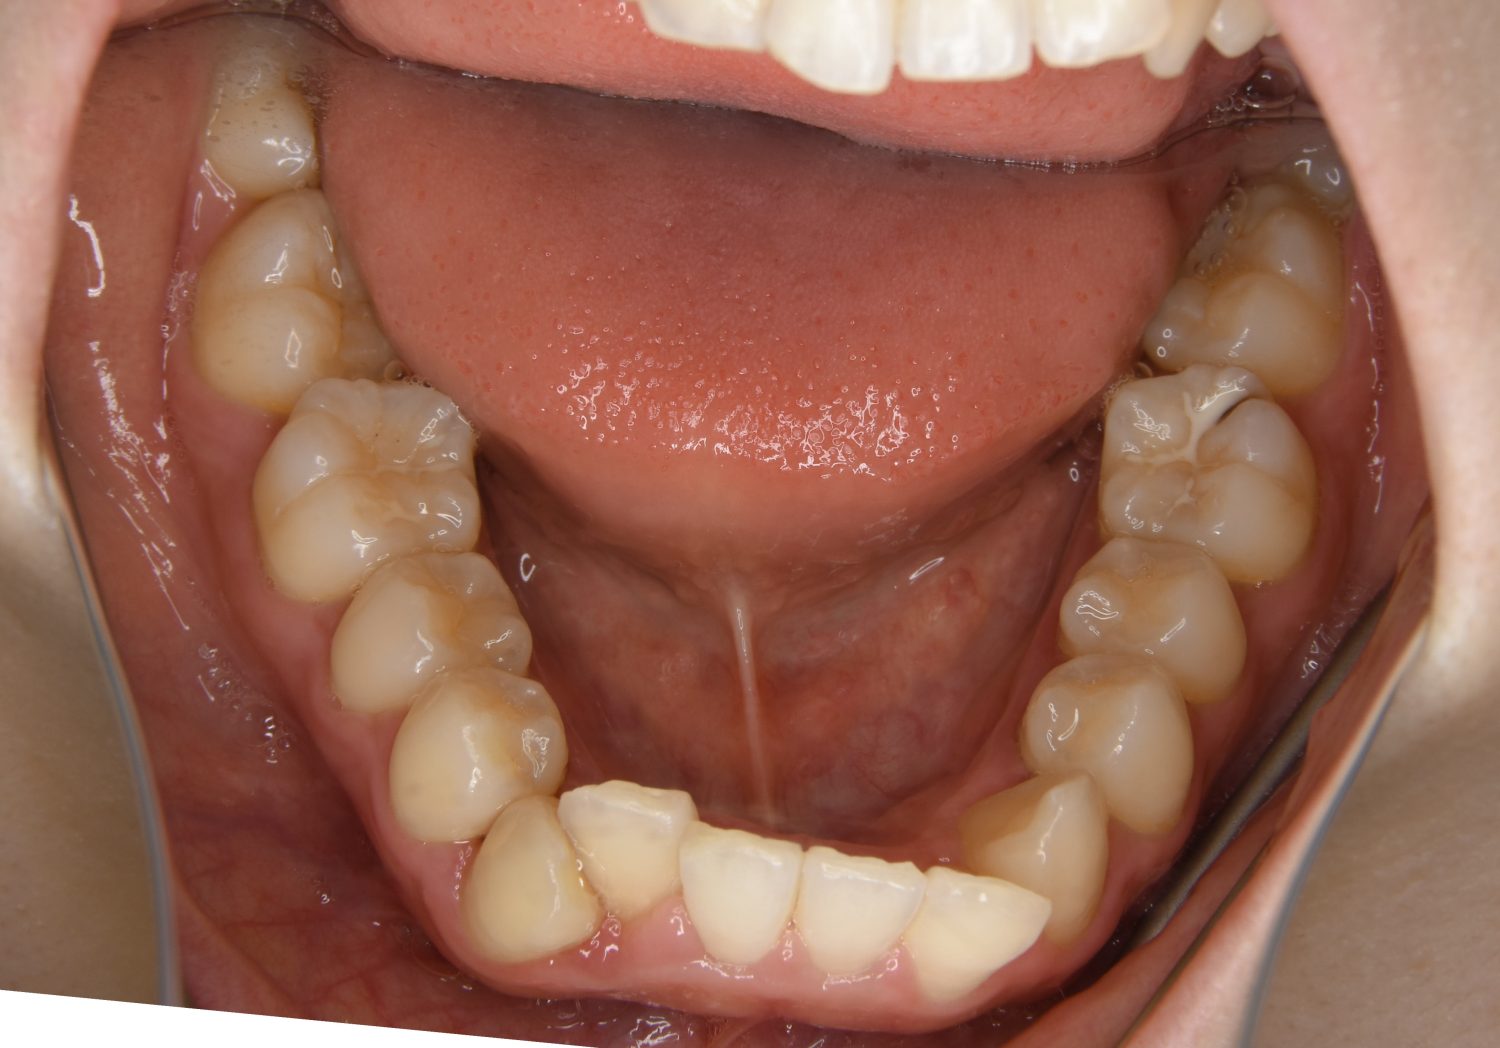

叢生の症例紹介②

Before

After

主訴

歯の凸凹を治したい。

治療内容

アライナー(インビザライン)にて非抜歯で治療を行いました。

上下前歯部に叢生(凸凹)が認められる状態でした。歯列の遠心移動を行うことで機能面および審美面が改善されました。